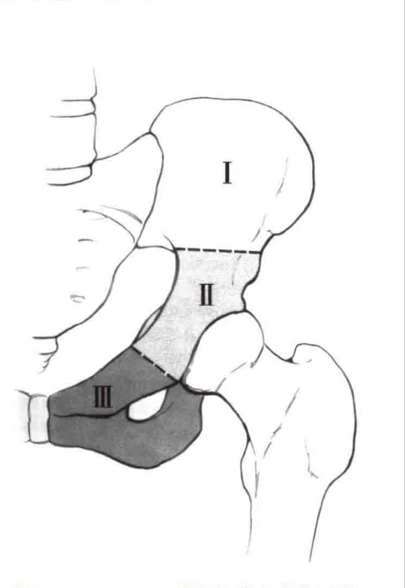

近年来,随着医学科学技术的发展尤其是3D打印技术在骨肿瘤精准切除和关节功能重建方面的应用,对于II区暨髋臼区肿瘤的精准切除和使用金属3D打印个性化的半骨盆假体替代切除后的骨缺损重建髋关节功能成为可能。钟华介绍,业内一般把盆骨肿瘤按髂骨区,髋臼区,耻骨、坐骨区分成三区(图6)。当骨盆环遭到肿瘤破坏时,其承受能力将明显改变,可因肿瘤的发生的部位不同而症状不同,轻者坐、站、走,运动时产生不适疼痛,重者轻微活动引起病理性骨折。不同区域的肿瘤也有不同的手术切除重建的方法。

图6 Enneking骨盆肿瘤分区